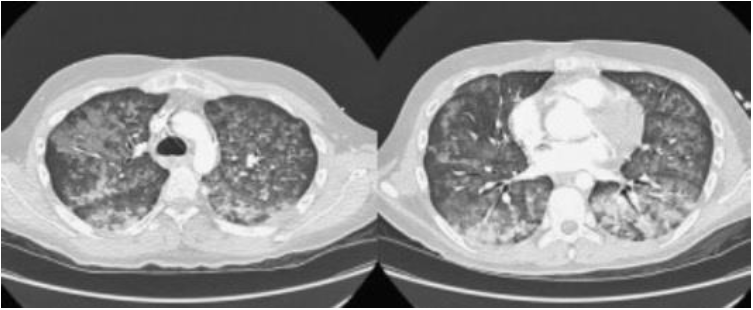

Jovem de 20 anos estava hígido até duas semanas atrás, quando começou a apresentar desconforto torácico e fraqueza de membros. Ao exame: PA = 120/90mmHg; FC = 75bpm; FR = 24irpm; temperatura axilar = 36,3ºC. Exame cardiovascular sem alterações, mas com estertores crepitantes nos 1/3 inferiores de ambos os pulmões. No hemograma: hematócrito = 30,7%; hemoglobina = 10,4g/dL; plaquetas = 345mil/µL; leucograma = 14.500/µL; ureia = 214mg/dL; creatinina = 30mg/dL; potássio = 5,5mEq/L; sódio = 141mEq/L; cálcio = 7,6mg/dL; fósforo = 7,3mg/dL; magnésio = 3,0mg/dL; proteína total = 5,1g/dL (albumina 2,1g/dL); AST = 18ui/L; ALT = 14ui/L com EAS apresentando 3+ de proteína. Os complementos séricos estavam normais e os seguintes exames foram negativos: HBsAG, antiHCV, FAN e ANCA. Iniciado procedimento de hemodiálise, no 4º dia de hospitalização, apresentou hemoptise volumosa com instabilidade hemodinâmica. Foi para o centro de terapia intensiva e realizou tomografia computadorizada de tórax (conforme imagem a seguir). A dosagem do anticorpo antimembrana basal glomerular foi de 257EU/mL (valor de referência: < 5EU/mL).